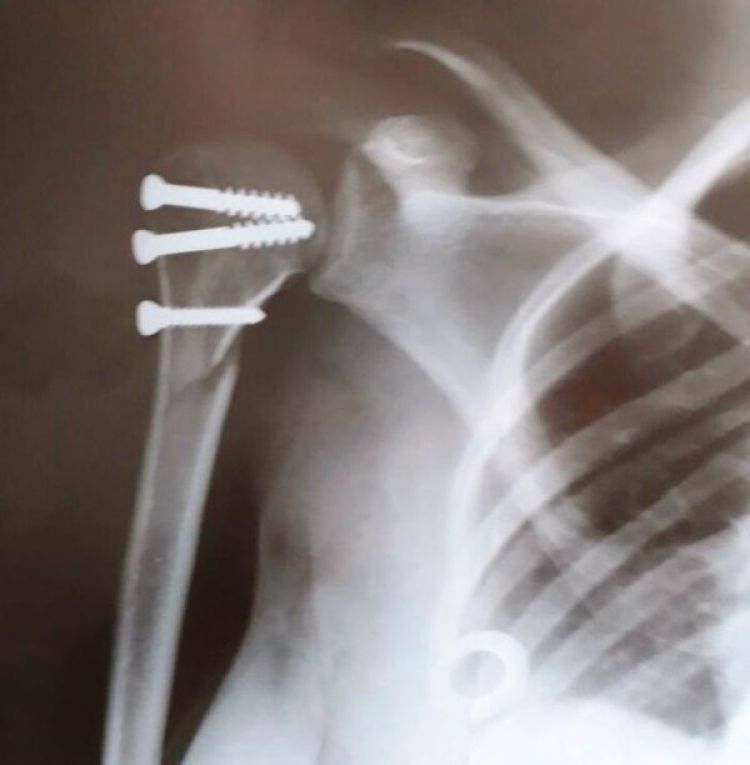

Com a queda, Eduarda fraturou o braço direito e foi imediatamente encaminhada à emergência. No dia seguinte, pela manhã, após realizar um exame de raios-X, foi constatado que o braço dela estava quebrado. “Eles me internaram, para que eu pudesse fazer a cirurgia que colocaria o meu ombro no lugar novamente. Até então, apesar do braço quebrado, eu movimentava as mãos normalmente”, explica.

A cirurgia ocorreu em 11 de setembro e, no dia seguinte, Eduarda notou que não estava sentindo o braço direito. Ela relatou o fato a uma enfermeira, que lhe disse ser normal, por conta da anestesia, mas que em dois dias ela voltaria a sentir o braço normalmente.

O problema é que passou uma semana e ela ainda não sentia o braço. Voltou para a consulta de retorno com o médico do hospital e, com exames, ele constatou que tinha sofrido uma lesão do plexo braquial. “E isso aconteceu durante a cirurgia, eles lesionaram meu nervo”, conta.